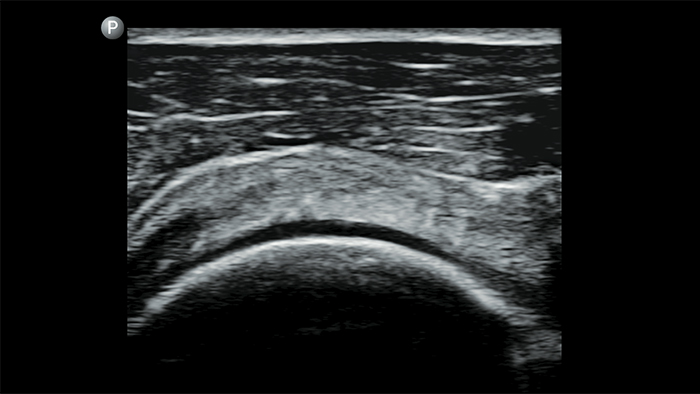

Keep an eye on COVID pneumonia

Lumify can help give results similar to a chest CT when evaluating pneumonia and adult respiratory distress syndrome.